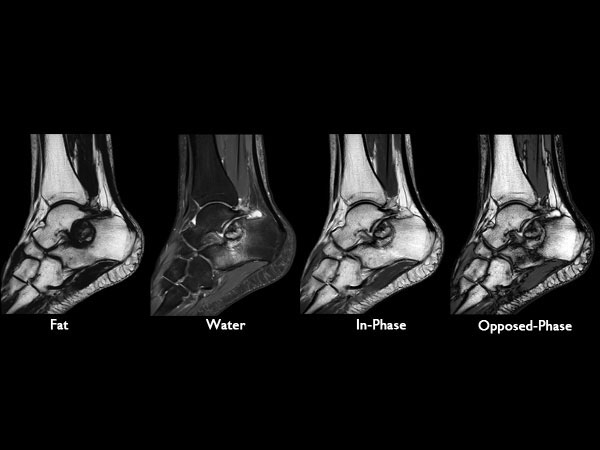

Sagittal T1w mDIXON (post gado)